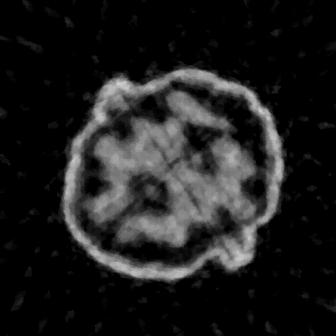

The numerical results are summarized in Table 1. These are evaluated in terms of peak signal-to-noise ratio (PSNR) and structural similarity index (SSIM) considering three different sampling settings, with different sparsity levels , angles, and noise set to 1% AWGN. It is evident that our method, TomoSelfDEQ, outperforms the competing approaches in terms of both PSNR and SSIM. In Fig. 1, we report the results obtained with the different methods considering 64 (top row), 32 (middle row) and 16 (bottom row) angles. We can see that with TomoSelfDEQ was able to reconstruct sharp and neat boundaries, even though some finer details are lost due to over-smoothing in certain regions. In addition, TomoSelfDEQ accurately reconstructs constant patches, without adding any significant artifacts and it proves to be stable with respect to the reduction of angles. On the other hand, FBP reconstructions are noisy and show an increasing number of streaking artifacts as the number of angles decreases. In the TV regularized reconstructions, the staircasing behavior is evident, and the sharpness of the boundaries deteriorates as the number of angles decreases. Sparse2Inverse produces reconstructions with clear artifacts, particularly when only 16 angles are considered.

Similar consideration can be drawn for the reconstructions in Fig. 2, where we show reconstructions of different walnut slices in the most challenging setting, i.e., with 16 angles. From the close-ups it is clear that Sparse2Inverse introduces numerous noisy artifacts, compromising the reconstructions, while TomoSelfDEQ better preserves objects shapes, significantly reducing noise presence. A note is, however, in order on the comparison with Sparse2Inverse. While both methods share key ideas such as operating in both image and projection domains, computing losses in the projection domain, and avoiding explicit nullspace assumptions, TomoSelfDEQ differs fundamentally in several important aspects. First, while Sparse2Inverse uses a standard U-Net architecture, our method leverages DEQ to implicitly represent an infinite-depth network. Second, TomoSelfDEQ provides theoretical guarantees about matching supervised performance, while Sparse2Inverse relies primarily on empirical validation. These theoretical and architectural advantages translate into practical improvements, as demonstrated in our numerical results where TomoSelfDEQ consistently outperforms Sparse2Inverse across different undersampling rates (cf. Table 1).